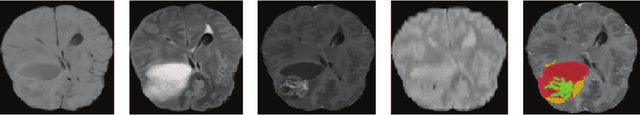

Abstract:In the field of multimodal segmentation, the correlation between different modalities can be considered for improving the segmentation results. Considering the correlation between different MR modalities, in this paper, we propose a multi-modality segmentation network guided by a novel tri-attention fusion. Our network includes N model-independent encoding paths with N image sources, a tri-attention fusion block, a dual-attention fusion block, and a decoding path. The model independent encoding paths can capture modality-specific features from the N modalities. Considering that not all the features extracted from the encoders are useful for segmentation, we propose to use dual attention based fusion to re-weight the features along the modality and space paths, which can suppress less informative features and emphasize the useful ones for each modality at different positions. Since there exists a strong correlation between different modalities, based on the dual attention fusion block, we propose a correlation attention module to form the tri-attention fusion block. In the correlation attention module, a correlation description block is first used to learn the correlation between modalities and then a constraint based on the correlation is used to guide the network to learn the latent correlated features which are more relevant for segmentation. Finally, the obtained fused feature representation is projected by the decoder to obtain the segmentation results. Our experiment results tested on BraTS 2018 dataset for brain tumor segmentation demonstrate the effectiveness of our proposed method.

Abstract:In the field of multimodal segmentation, the correlation between different modalities can be considered for improving the segmentation results. In this paper, we propose a multi-modality segmentation network with a correlation constraint. Our network includes N model-independent encoding paths with N image sources, a correlation constraint block, a feature fusion block, and a decoding path. The model independent encoding path can capture modality-specific features from the N modalities. Since there exists a strong correlation between different modalities, we first propose a linear correlation block to learn the correlation between modalities, then a loss function is used to guide the network to learn the correlated features based on the linear correlation block. This block forces the network to learn the latent correlated features which are more relevant for segmentation. Considering that not all the features extracted from the encoders are useful for segmentation, we propose to use dual attention based fusion block to recalibrate the features along the modality and spatial paths, which can suppress less informative features and emphasize the useful ones. The fused feature representation is finally projected by the decoder to obtain the segmentation result. Our experiment results tested on BraTS-2018 dataset for brain tumor segmentation demonstrate the effectiveness of our proposed method.